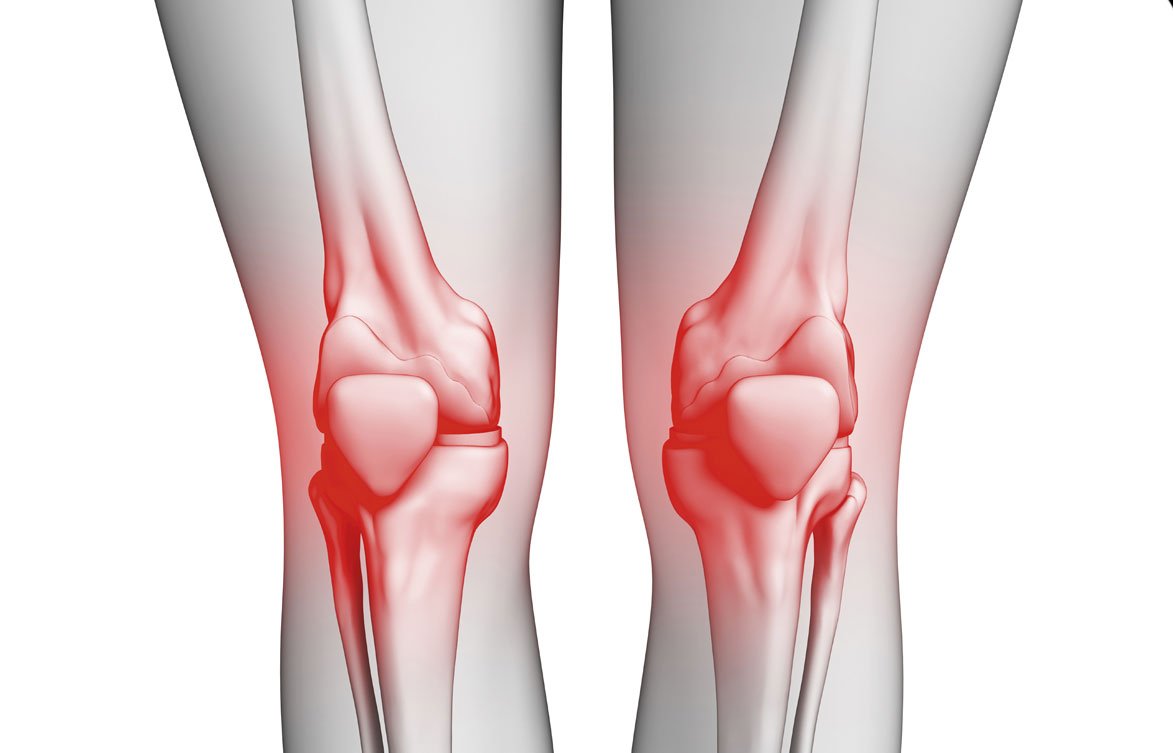

تُعد مشاكل الركبة من أكثر الشكاوى الطبية شيوعًا، لا سيما مع التقدم في العمر أو نتيجة للإصابات الرياضية أو الإجهاد المتكرر. ومن بين هذه المشكلات، يأتي تآكل أو إصابة غضروف الركبة كسبب رئيسي للشعور بالألم وصعوبة الحركة. لكن هل الجراحة هي الحل الوحيد؟ الجواب هو لا.

ما هو غضروف الركبة وما أهميته؟

غضروف الركبة هو نسيج مرن وناعم يُغلف أطراف العظام داخل مفصل الركبة، ووظيفته الأساسية:

- امتصاص الصدمات

- تسهيل حركة المفصل

- منع احتكاك العظام ببعضها

عندما يتعرض الغضروف للتآكل أو التمزق، يشعر المريض بألم حاد، خاصة أثناء الحركة أو عند ثني الركبة، مما يؤثر سلباً على جودة الحياة.